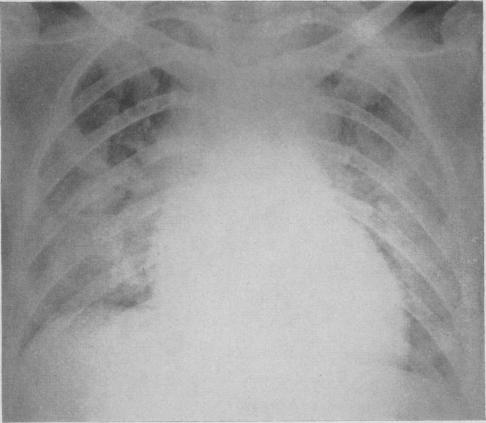

Pulmonary complications during treatment with hexamethonium.

Can Med Assoc J. 1955 Mar 15;72(6):448-51.